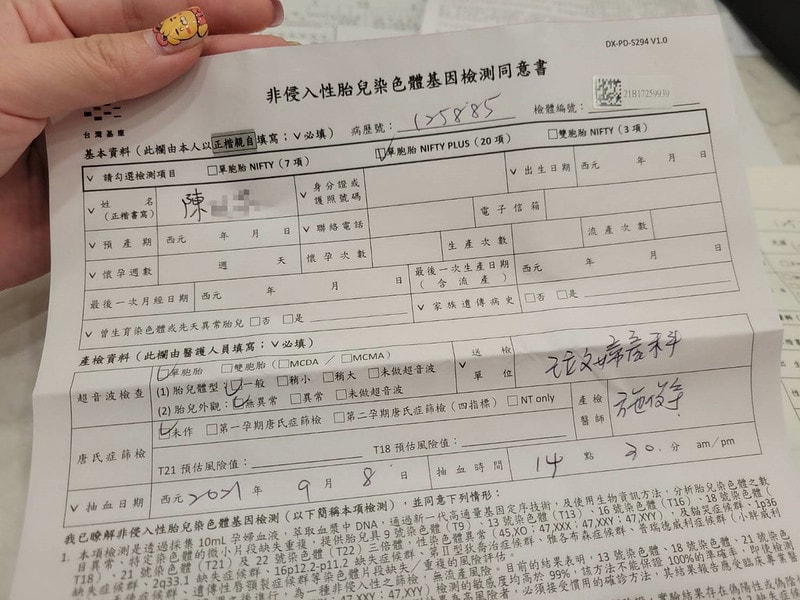

我做了NIPT+五合一+子癲前症總共大概三樣檢查

花了三萬二左右

14周前一定要先做NIPT

我記得這天好像抽了五管血

然後就是要填一堆表格

非侵入性胎兒染色體檢測

我的診所有7項、20項、94項

費用從15000~38000都有

簡單來說做越多費用就越高啦

看你們自己預算上的考量

但基本上是建議一定要做的

因為高齡產婦生出唐氏症小孩的機率比較高

對的,我後來沒選擇做羊膜穿刺

只有做了NIPT

NIPT只要抽血就好了